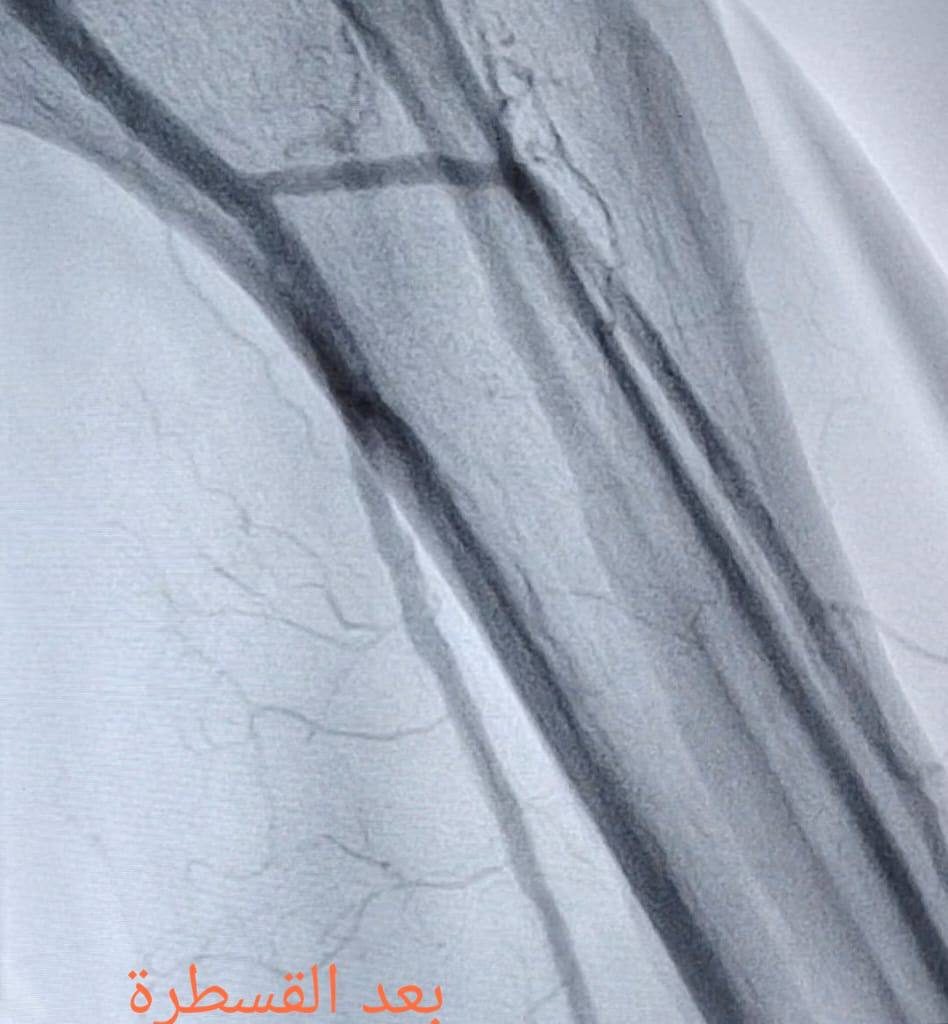

“تم إجراء عمليتين للقسطرة الشريانية، حيث عملنا على فتح الانسدادات في الشرايين الطرفية وعلاج قصور الشرايين، ما ساهم في إعادة جريان الدم إلى الساقين والقدمين بعد أن كانت الحالتان مهددتين بالبتر.”

“الحمد لله، تكللت العمليتان بالنجاح، وتم استعادة التروية الدموية بشكل جيد، الأمر الذي ساعد على إنقاذ الساقين من البتر.”